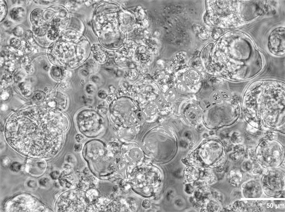

纳米复合材料水凝胶的表征和生物相容性 (Hayeon et al., 2024)

将 TSrP 嵌入 GelMA 水凝胶,通过光交联形成 G-TSrP 复合水凝胶,兼顾生物相容性与功能稳定性:

结构与力学适配:TSrP 均匀分散于水凝胶内部,增加孔隙率和溶胀率,同时降低杨氏模量,提升材料柔韧性与组织适配性。

ROS 清除与生物安全:G-TSrP 表现出剂量依赖性 ROS 清除能力,且对成纤维细胞、角质形成细胞和内皮细胞无细胞毒性。

可控缓释特性:水凝胶可实现 TA 与 Sr²⁺的持续释放,24 小时释放量分别达 10μM 和 500μM,均处于生物安全浓度范围。